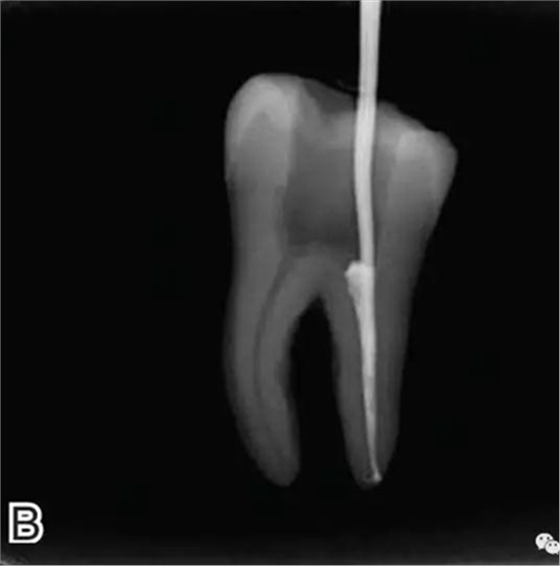

1、選擇攜熱器工作尖

根據(jù)預(yù)備后根管的粗細(xì)選擇相應(yīng)型號(hào)的攜熱器工作尖。

要求工作尖能自由到達(dá)距根尖4~5 mm(有學(xué)者提出3~4 mm)的位置并能輕微接觸根管壁,用橡皮片做好標(biāo)記(圖1)。

圖1 選擇攜熱器工作尖,A.試攜熱器尖 B.工作尖在根內(nèi)的位置